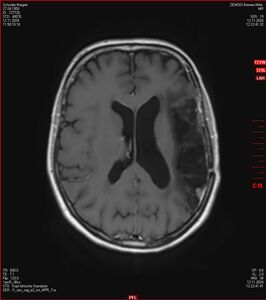

MRT vom 12. November 2024

So nun ein paar neue Bilder aus meinem Kopf. (Durch klicken bekommt man eine größe Ansicht eines Einzelbildes).

Die letzten drei Bilder Zeigen aus meiner Sicht den Tumor, der im Jahr 2021 bestrahlt wurde.